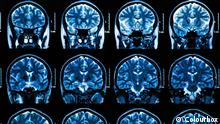

"En algunos pacientes, la función pulmonar podría disminuir entre un 20 y un 30 por ciento después de la recuperación", dice el médico Owen Tsang Tak-yin, director del Centro de Enfermedades Infecciosas del Hospital Princesa Margarita de Hong Kong. "Jadean cuando van un poco más rápido", agregó el galeno. La tomografía de algunos pacientes muestra una especie de neblina lechosa y vidriosa en los pulmones, lo que sugiere un daño en los órganos.

Los hallazgos de Hong Kong confirman las primeras investigaciones de Wuhan a principios de febrero de 2020. En un estudio, los científicos del Hospital Zhongnam de la Universidad de Wuhan analizaron 140 escáneres de pulmón de pacientes con coronavirus y encontraron una nube de aspecto lechoso y transparente en los pulmones de todos ellos.